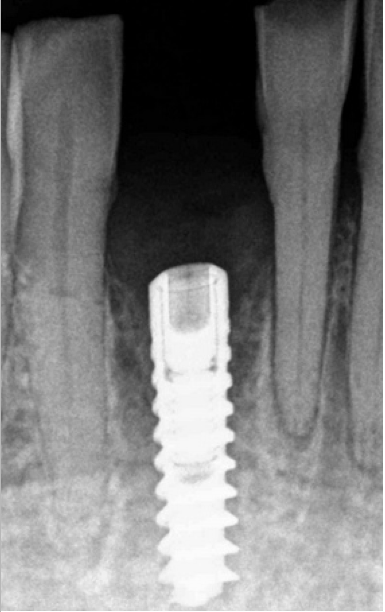

Implantologia nel settore 41. Il paziente ha perso l'elemento (già parzialmente compromesso parodontalmete) in seguito ad un trauma. Lo spessore della cresta in questa sede si presenta molto sottile tale da rendere necessaria un'espansione crestale durante l'inserimento della fixture implantare.